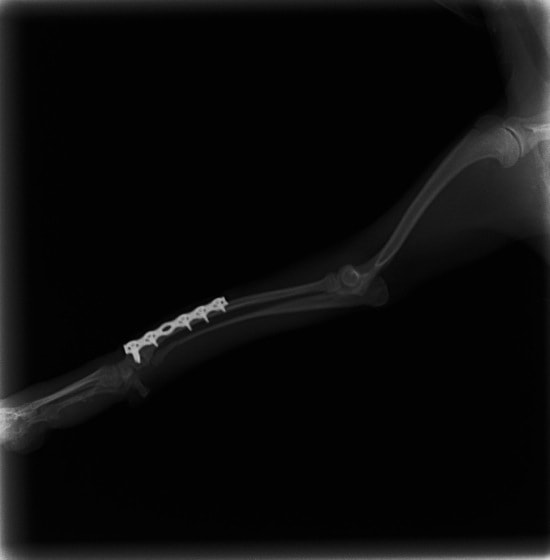

トイプードル 右遠位橈尺骨短斜骨折のALPSによる内固定

当院ではAdvanced Locking plate system(ALPS)と、Locking compression plate system(LCPS)という骨接合法で骨折症例の治療を行っています。

Advanced Locking Plate System

従来型のプレートのように広い面積で骨と接するプレートを用いて固定を行った場合、プレート下の骨はプレートとの接触面において血行が絶たれ壊死し、それがリモデリングされると骨密度が低下する。この骨密度の低下防ぐために、骨折部局所への血行を温存することの重要性が近年改めて認識されるようになってきている。Advaed Locking Plate System (ALPS)は従来型のプレートシステムの欠点を改良し、より使いやすく、より骨への血行を阻害しないようにというコンセプトで作られた。